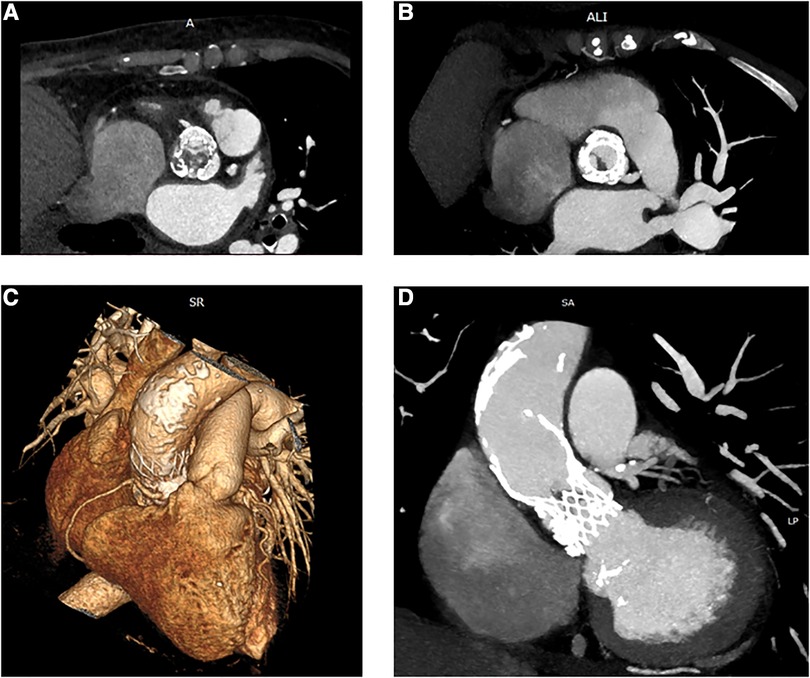

In November 2021, she was admitted to our emergency department due to fatigue, exertional dyspnea, and intermittent fever for 3 weeks, treated with empirical antibiotics. Electrocardiography demonstrated sinus rhythm, 70 beats/min, with features of left ventricle hypertrophy. The blood sample revealed moderate leukocytosis and 1.14 μg/L procalcitonin. Blood cultures were positive for Staphylococcus aureus. Both transthoracic echocardiogram (TTE) and transesophageal echocardiography (TEE) revealed large, mobile vegetation on the aortic prosthesis and non-structural valve dysfunction (NSVD) with a mean gradient of 54 mmHg. Angio-CT scanning showed thrombosis between the left coronary and non-coronary cusps of the prosthesis (Figure 1) and splenic embolization. Antibiotic therapy was started, guided by an antibiogram. Despite initial clinical improvement, 8 days after hospitalization, the patient developed a fever recurrence and initial hemodynamic deterioration requiring intensive care unit admission. Although the patient was previously discarded for surgery, TAVI-IE at this time was considered a surgical indication, despite the very high-risk score (STS PROM: 10.38%). After a full sternotomy, cardiopulmonary bypass (CPB) was set using the right axillary artery (by the interposition of a Dacron graft) and the right atrium. Aorta was clamped (in the upper zone 0), and Del Nido cardioplegia was administered. Through transverse aortotomy, the prosthesis was excised with the native aortic valve. The prosthesis was entirely covered by fibrotic tissue, and signs of endocarditis were also detected. Moreover, between the last part of the Valsalva sinus and the sinotubular junction, the aortic lumen was narrowed by a full-thickness circumferential calcified shelf, in this case described as an aortic sinotubular ridge. Due to this challenging anatomy, only the Perceval (Livanova, London, UK) S (small) sizer was suitable. In addition, considering the extremely calcified aorta and coronary ostia, the option to perform a Bentall-De Bono or an enlargement of the aortic root procedure was judged hazardous. Therefore, first, ascending aorta was replaced with a 24-mm Dacron tube to allow safe deployment of the sutureless valve, Perceval S, followed by ballooning. In addition, the aortic sinotubular ridge thickening did not allow placing the three standard guide stitches used for Perceval deployment. Therefore, only one guide stitch was used to parachute down the prosthesis (Figure 2). No extra stitches were used to anchor the valve to the Dacron graft. CPB was easily discontinued under TEE monitoring, demonstrating that the prosthesis was well-functioning. The explanted prosthesis was sent for microbiology analysis, and the result showed growth only for Gram-positive aerobic pathogens. The patient was extubated after 6 h and discharged to rehab on postoperative day 20. After 15 months of follow-up, no negative events were reported. Follow-up TTE showed preserved left ventricular ejection fraction (LVEF) and a well-functioning aortic prosthesis (mean gradient of 19 mmHg, no regurgitation).

Figure 1. Preoperative CT: axial view of the CoreValve prosthesis with vegetations in the left (A) and right (B) coronary cusps. 3D reconstruction of the ascending aorta with features of porcelain aorta (C). Multiplanar reconstruction (MPR) shows thrombosis and vegetation inside the CoreValve scaffold and prominent calcification of the aorta (D).